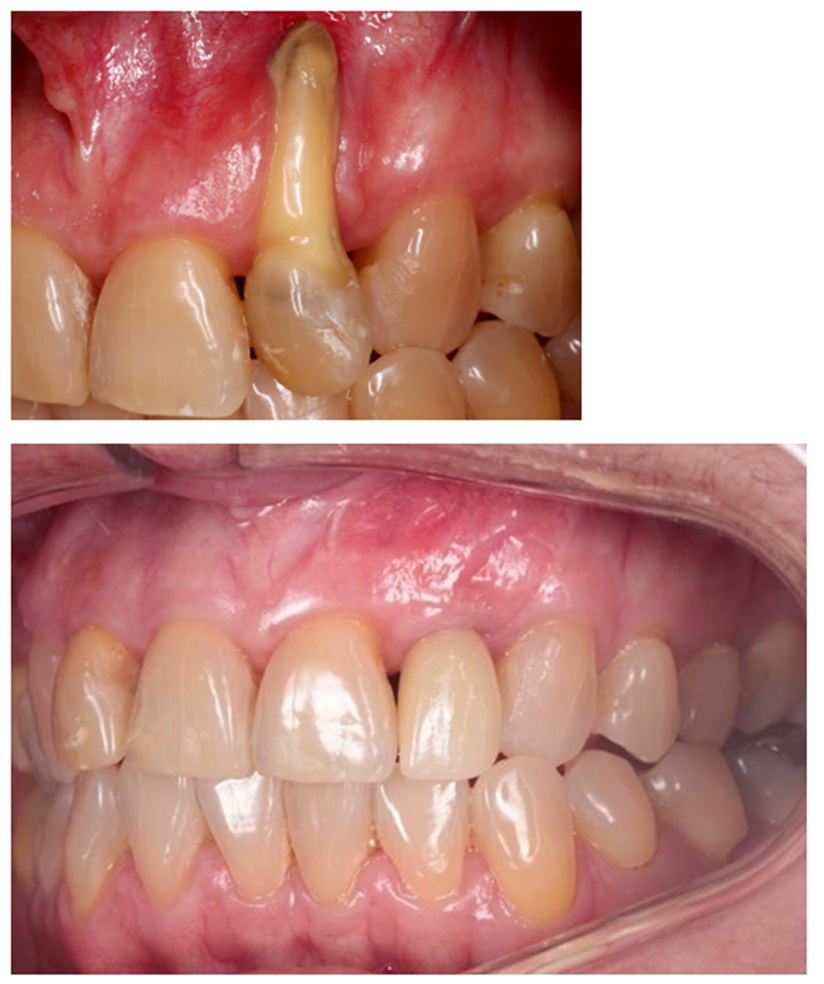

Sorrisos harmônicos e belos são cada vez mais almejados pelos pacientes que buscam tratamentos odontológicos, principalmente nos casos com patologias e/ou ausência de dentes anteriores. Além disso, vivemos em uma sociedade em que as pessoas possuem expectativas e exigências altas nos procedimentos com finalidade estética. Neste sentido, as técnicas de preservação alveolar são amplamente utilizadas em casos de manutenção do rebordo alveolar na região anterior da maxila quando se deseja instalar implantes osseointegráveis. Esta abordagem justifica-se pelo fato da reabsorção óssea ocorrer naturalmente após a perda dos elementos dentários. Nos casos em que a perda óssea vestibular é muito extensa e o tecido gengival é insuficiente, não há a possibilidade de preservar o volume ósseo imediatamente após a exodontia (Figuras 1 e 2).

Sendo assim, na dependência do nível de destruição dos tecidos de suporte/proteção dental, a presença de defeitos de tecido duro e/ou mole podem dificultar o restabelecimento da estética e da função mastigatória, ou até mesmo impedir a realização de reabilitação implantossuportada.

Nossa proposta é relatar o caso clínico da paciente M. S., que procurou a clínica do Curso de Especialização de Implantodontia da Universidade Paulista (Grupo Apoio) devido à condição do dente 22. Uma vez que a destruição periodontal era muito extensa, incluindo o ápice dental, foi indicada a exodontia do dente 22. Buscando reduzir o número de procedimentos cirúrgicos e o tempo necessário para a finalização do caso, foi realizada a reconstrução óssea imediatamente após a remoção do dente. Foi realizada a técnica de Regeneração Óssea Guiada (ROG) com membrana não absorvível de PTFE denso (Cytoplast), associada a enxerto ósseo xenógeno composto por 75% de hidroxiapatita e 25% de colágeno do tipo I (Extra Graft) (Vídeo 1 e Figura 3).